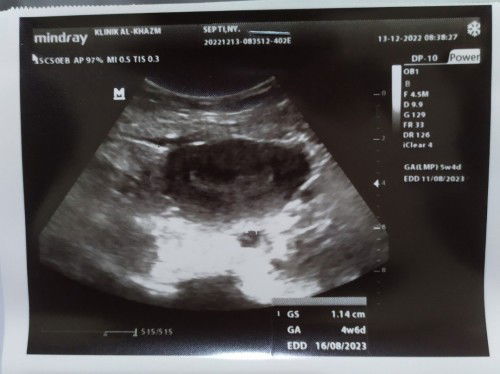

Saya hamil d sertai flek, di sni apa ad yang sama bund.. ? Banget khawatirnya,saya langsung USG hasilnyaa positif, cma baru kliatan kantong babyNya, ktanya msih trlalu kcil jdi gk bsa d liat dg jls.. N alhamdulillahnya msih bsa bertahan wlopun flek ringan..doakan saya ya bun agar saya dan baby sll sehat trs.. 🤲🏻 smoga bunda2 juga sht sll🤲🏻

iya itu hasil usg masih 4w6d bu